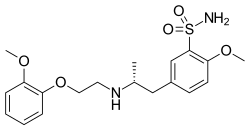

Alpha-1 blocker

The alpha blockers mostly act in our smooth muscles, especially the ones that control the size of vessels.[3] Thus, alpha1 blockers can dilate blood vessels and decrease the blood pressure.[3] Depending on its site of action, it can be used to treat different diseases.[3] They can be used to treat signs and symptoms of benign prostatic hyperplasia, hypertension (but not as first line agent), pheochromocytoma, extravasation management and reversal of local anesthesia.[3]

There are some off- label use as well, such as chronic prostatitis and lower urinary tract symptoms in males, ureteral calculus expulsion, ureteral stent-related urinary symptoms.[3] It can be used in post-traumatic stress disorder, Raynaud phenomenon, hypertensive crisis, extravasation of sympathomimetic vasopressors, problem with urine related to neurogenic bladder, functional outlet obstruction and partial prostate obstruction.[3]

Alpha-1 blocker

Alpha 1 blocker exerts its action on alpha-1 receptor, dilating the smooth muscles.[3] Alpha-1 receptor is a Gq type G-protein coupled receptor.[3] When it is activated, it will lead to activation of phospholipase C, raising the intracellular level of IP3 and DAG.[3] As a result, a higher intracellular concentration of Calcium is achieved, contributing to smooth muscle contraction and glycogenolysis.[3] Alpha 1 blockers, in contrast, bind to and act as inhibitors of alpha-1 receptors, hence preventing the downstream action mentioned(increase of phospholipase C, IP3 and DAG hence increase of Ca Concentration).[3] As a result, the contraction of smooth muscle is suppressed.